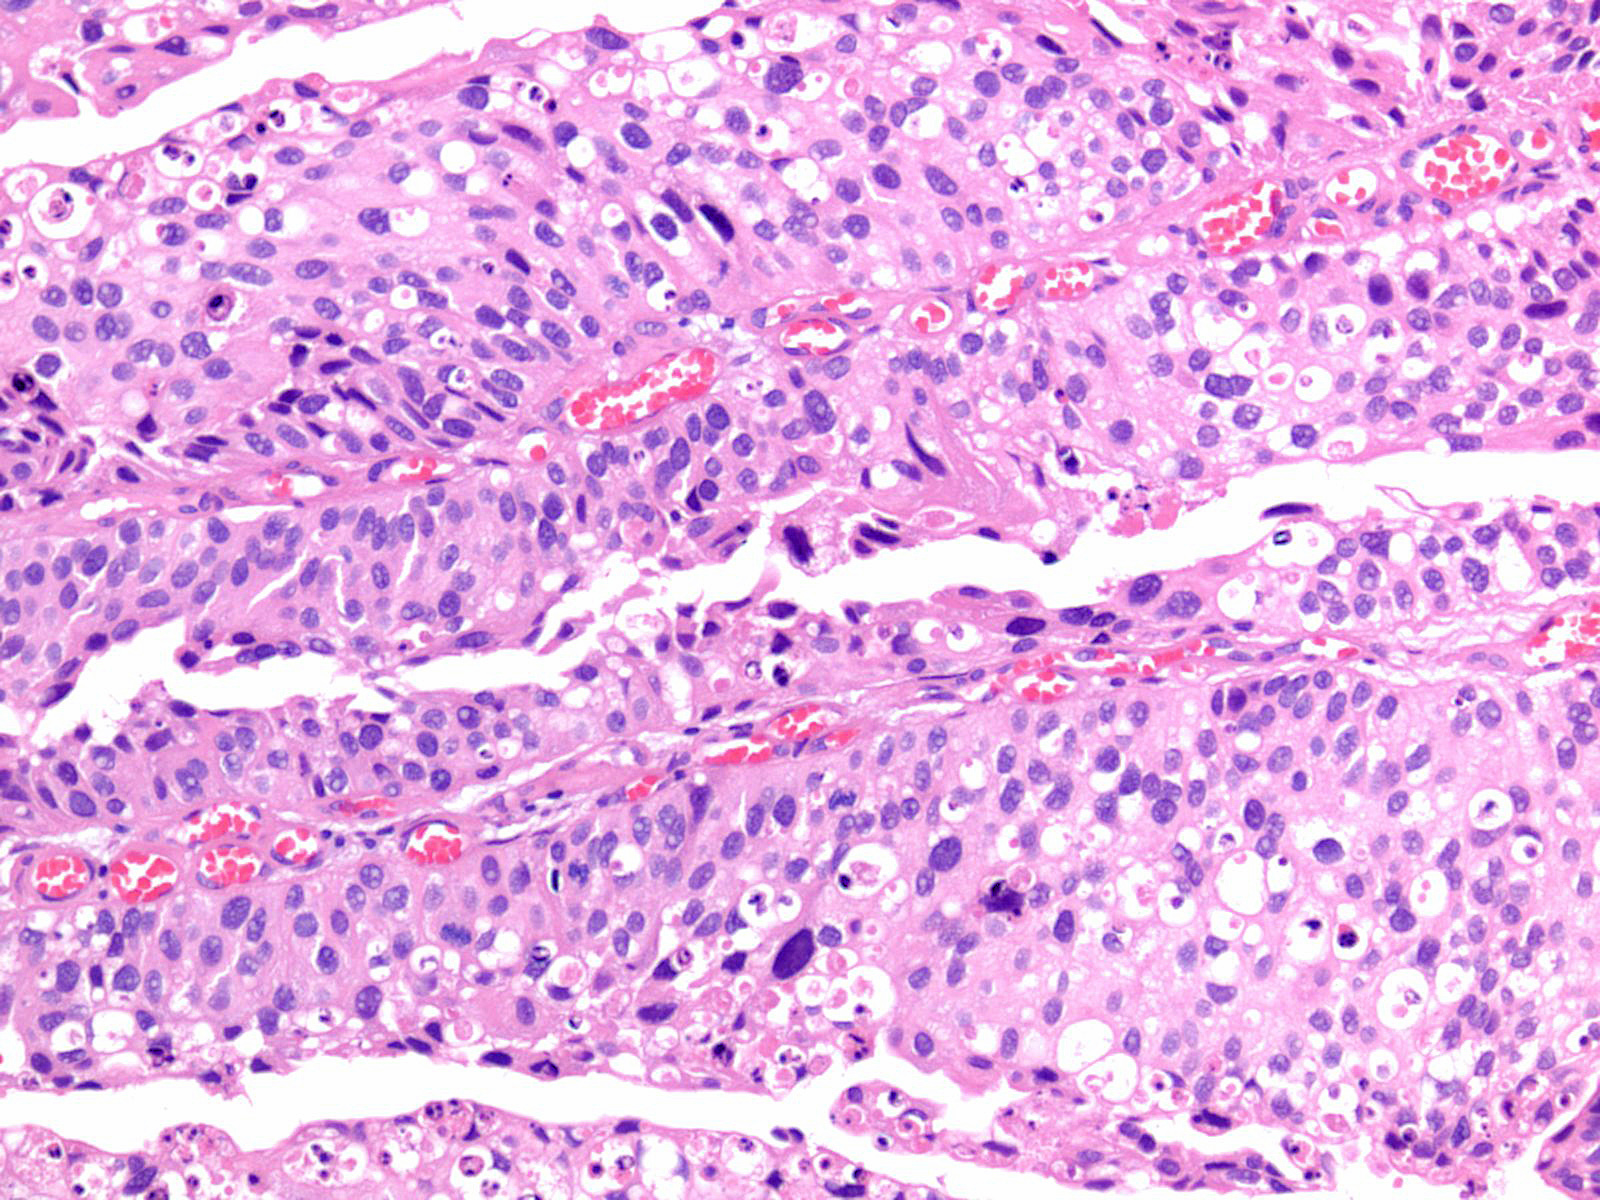

Bladder Papillary Lesions

Case ID: 212